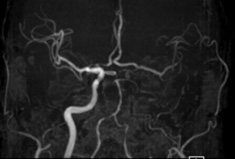

頭部MRA:左内頸動脈から左中大脳動脈(MCA)にかけての描出が不明瞭です。

術後のMRA:術前MRAと比較し左STAと左MCAと良好な血管吻合が確認できます。